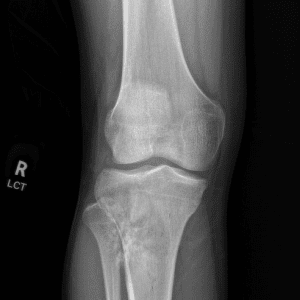

Pediatric Radiographs